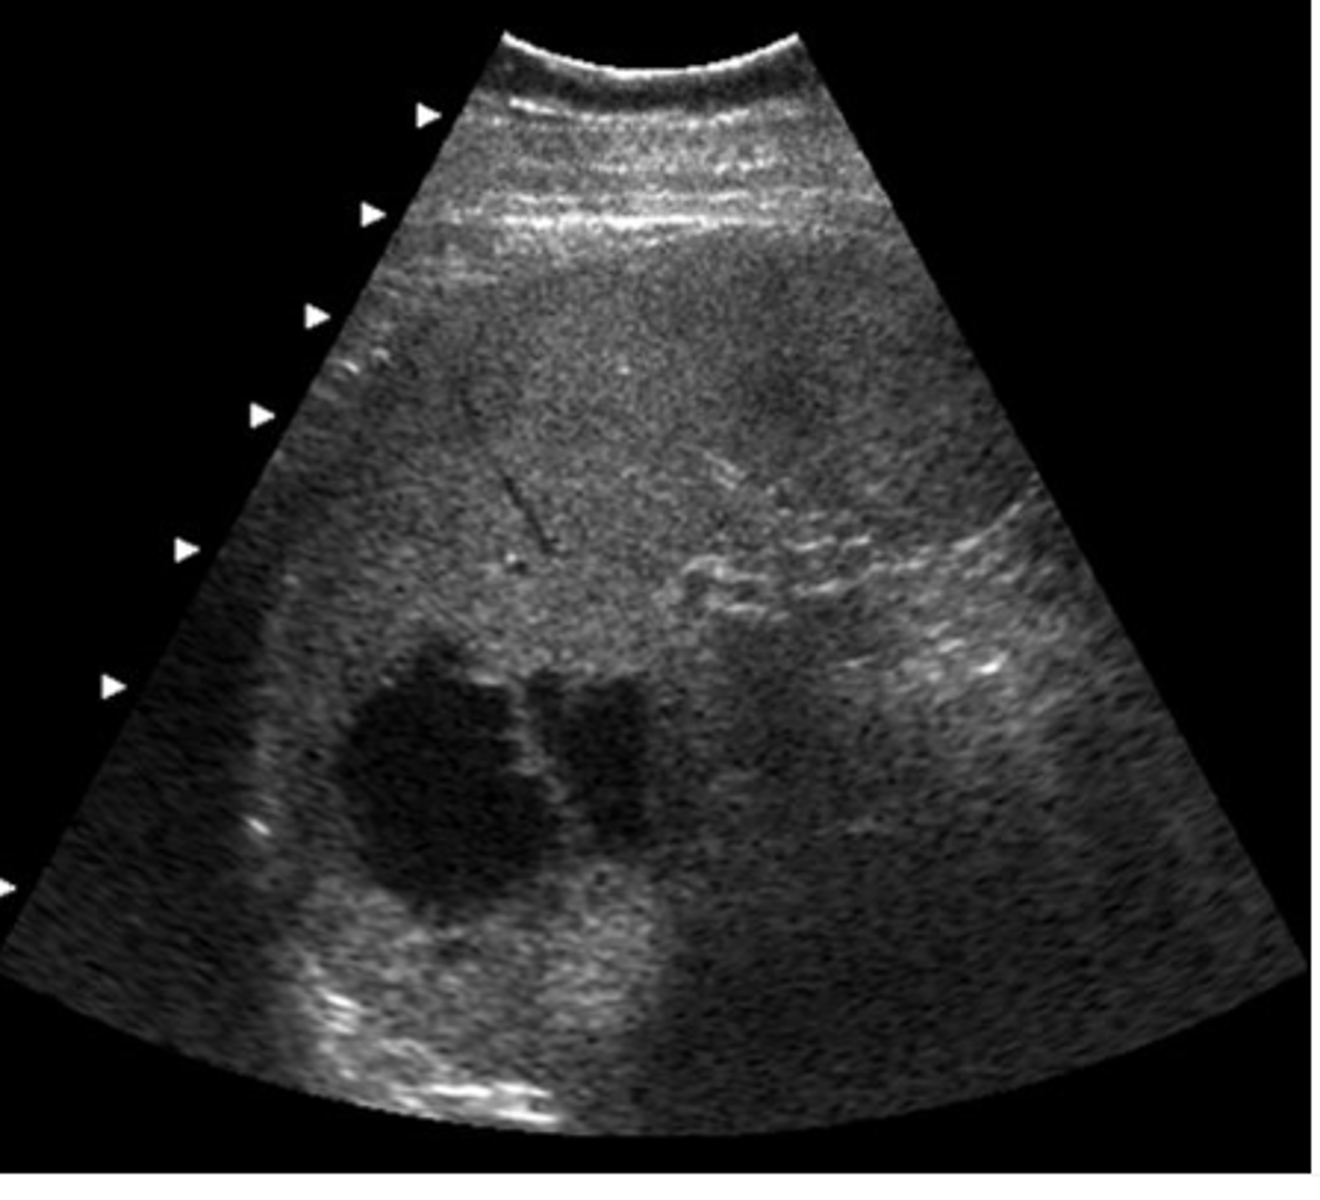

d. abdominal aortic aneurysm and horseshoe kidneys

This transverse image was obtained in the mid abdomen of a 57- year-old male with lower back pain. Which of the following correctly describes the sonographic findings?

a. leaking abdominal aortic aneurysm with hematoma

b. abdominal aortic aneurysm and para-aortic lymphadenopathy

c. inflammatory abdominal aortic aneurysm

e. abdominal aortic aneurysm with retroperitoneal fibrosis